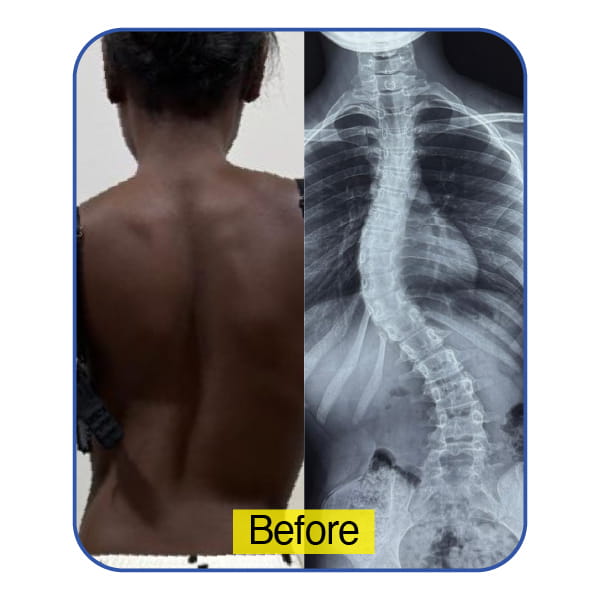

A 6-Year-Old from Zanzibar – Early Intervention, Lifelong Impact

A young child from Zanzibar presented with back pain and visibly uneven posture that was beginning to affect her daily activities and play. Detailed evaluation confirmed progressive scoliosis at a crucial growth stage.

Timely corrective surgery not only controlled curve progression but also preserved her spinal growth and overall development. Today, she enjoys a normal, active childhood — free from pain and limitation.